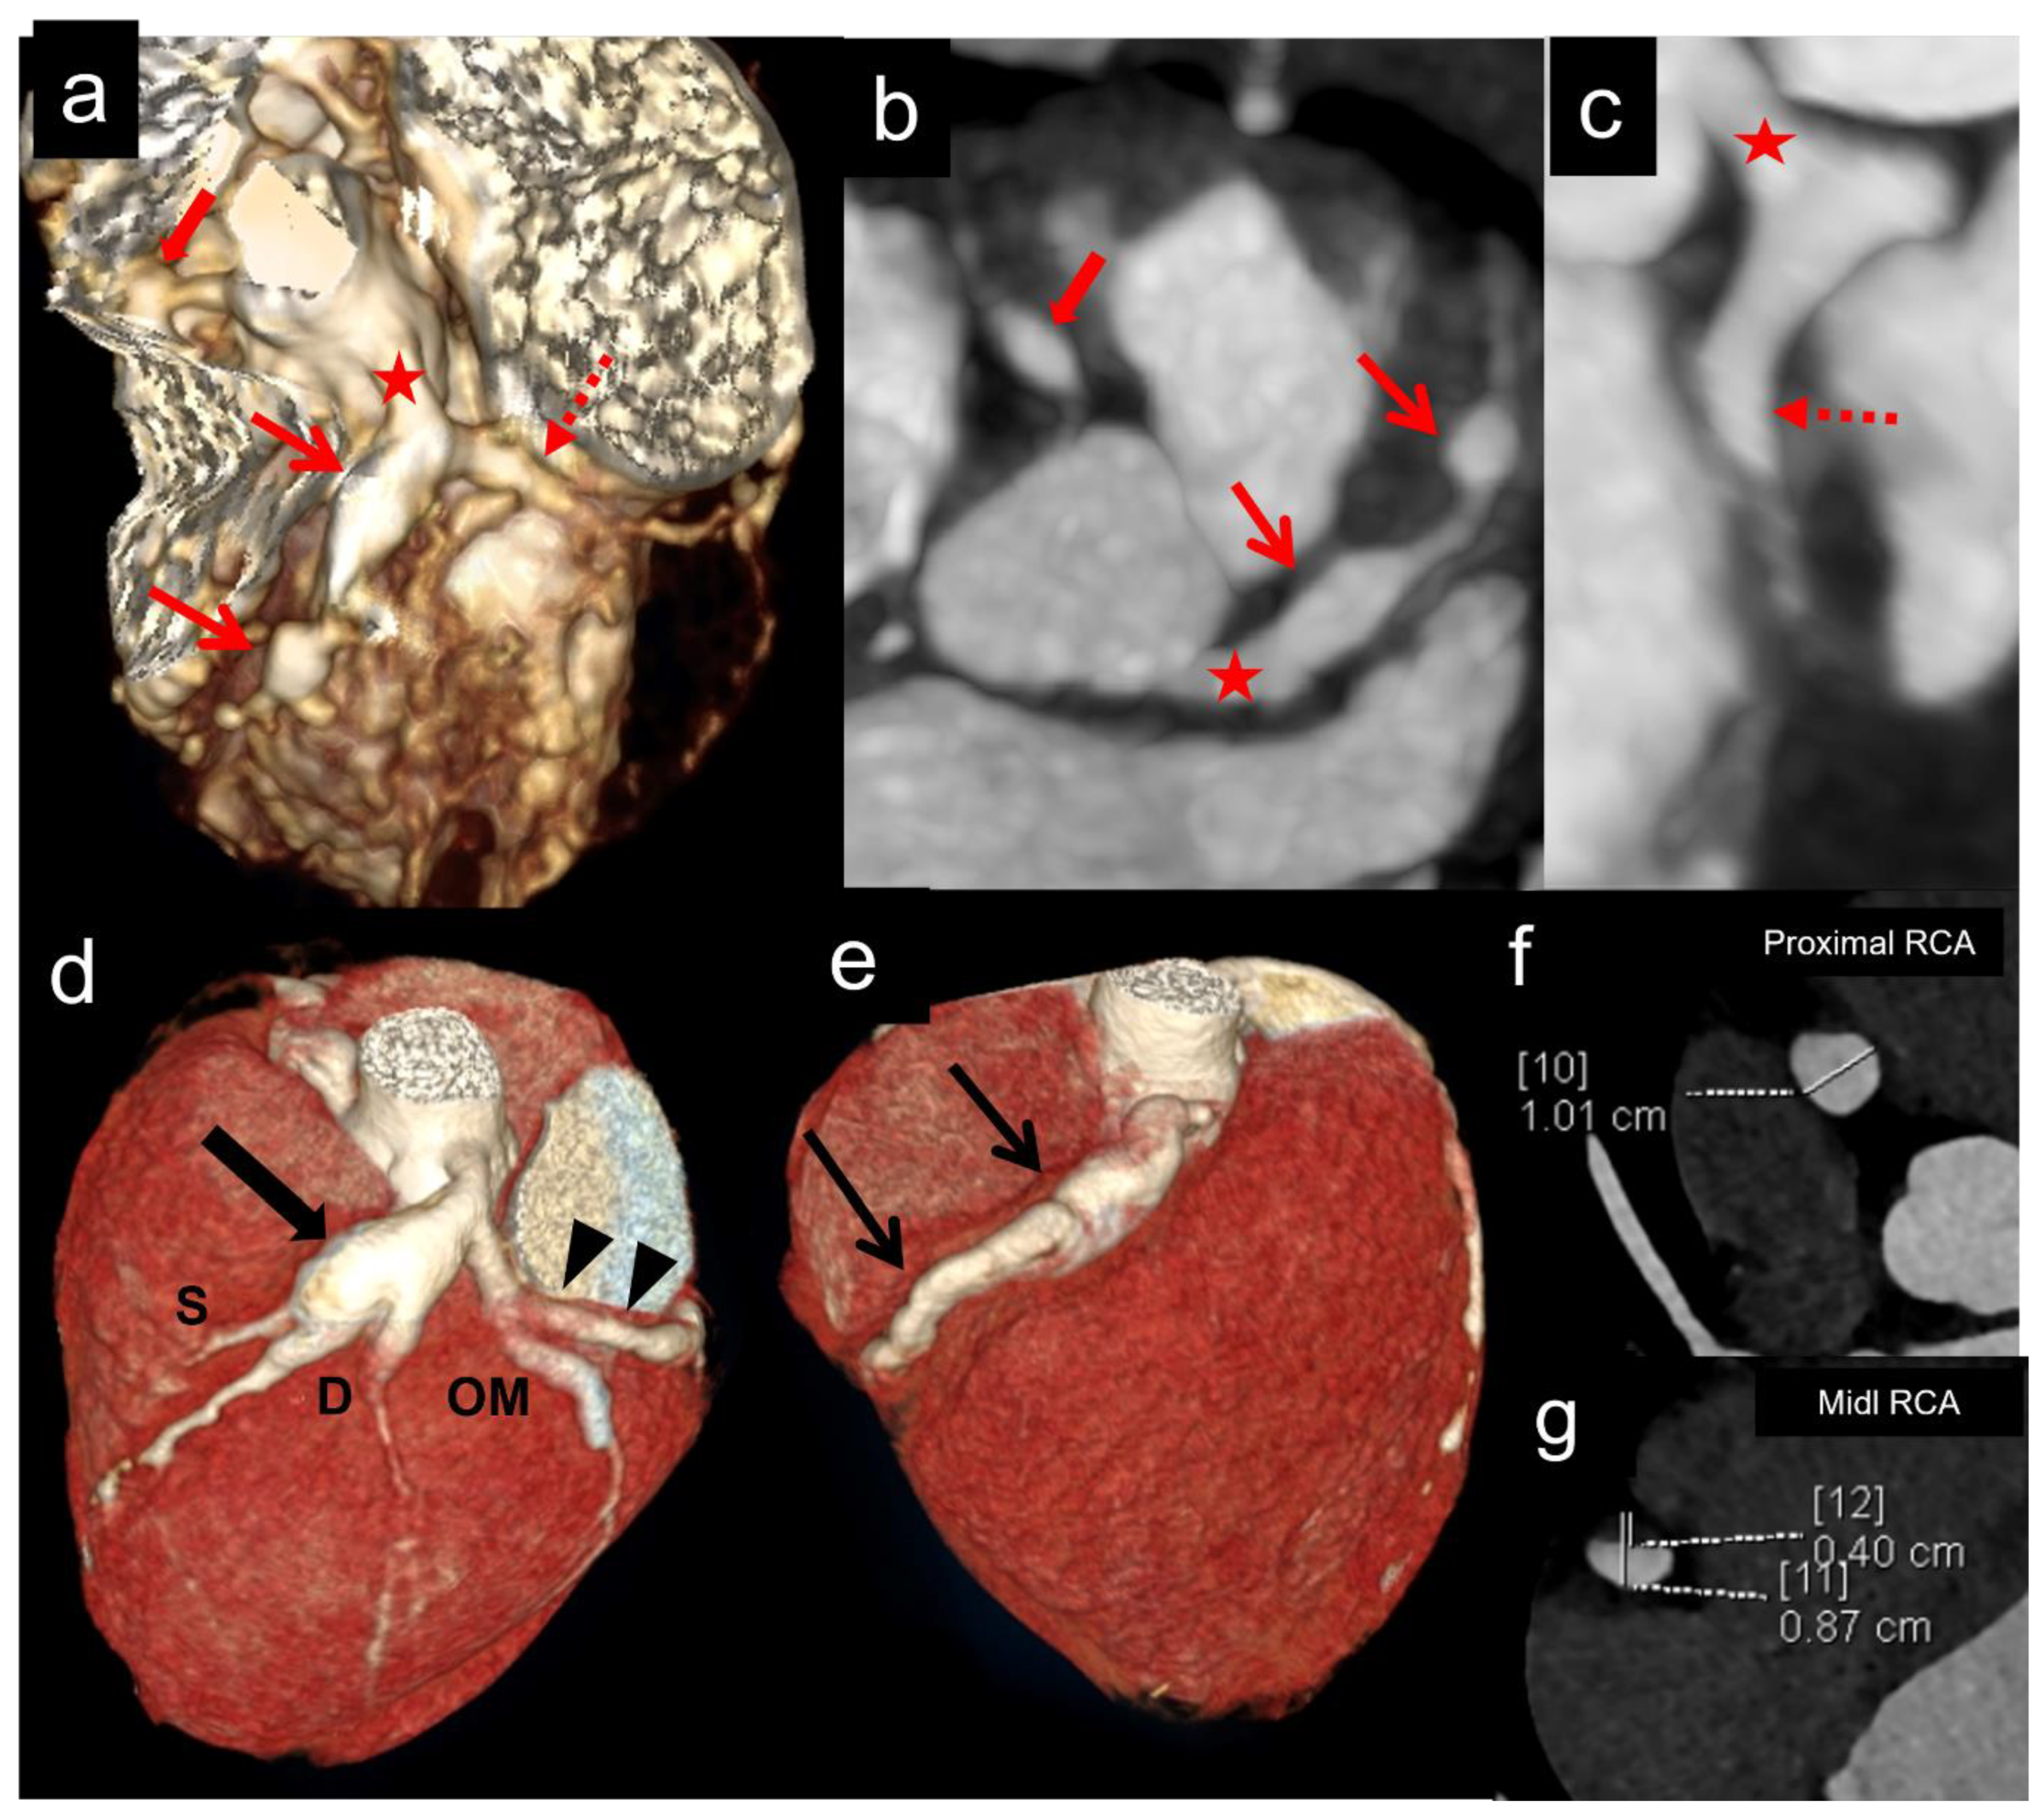

Figure 4. (ac) (Patient No.3 in Table 2): CT coronary angiography (CTCA) volume rendered (a,b) and curved reformatted of left anterior descending (LAD) (c) images in a 7 months male infant at presentation show fusiform aneurysm of right coronary artery (RCA) along its entire course with extension into posterior descending branch (PDA) (thick arrows in a,b). The left main coronary (LMCA) (asterisk in a,c), proximal and mid anterior descending (LAD) (thin arrows in a,c), and proximal left circumflex (LCX) (interrupted arrows in a) show fusiform aneurysms. Fusiform aneurysm is extending to involve the proximal segment of the obtuse marginal (OM) branch of LCX (arrowhead in a). Although TTE showed aneurysms in LMCA, proximal LAD, LCX, and RCA, it failed to demonstrate the distal extension of the aneurysm of RCA and involvement of the OM branch of LCX. (df) (Patient No.15 in Table 2): CTCA volume rendered (a,b) and curved reformatted images of RCA (c) in a 76 months boy at presentation show fusiform aneurysms of proximal left anterior descending (LAD) (thick arrows in a,b) and left circumflex (LCX) (thin arrows in d,e). RCA shows three discontinuous fusiform aneurysms in the proximal and mid segments (arrowheads in e,f). Although TTE showed aneurysms in proximal LAD, LCX, and RCA, it failed to demonstrate aneurysms in mid RCA.

Figure 5. (ac): (Patient No.12 in Table 2): CT coronary angiography (CTCA) volume rendered (a), axial (b) and curved reformatted images of left circumflex (LCX) (c) in a 2 months female infant at presentation show fusiform aneurysm of left main coronary artery (LMCA) (asterisk in ac) with extension into osteo-proximal segments of LAD (thin arrow in a,b) and LCX (interrupted arrow in a,c). Another non-contiguous aneurysm is seen in mid LAD (second thin arrow in a,b). Although TTE showed aneurysms in LMCA, proximal LAD, and RCA, it failed to demonstrate a second non-contiguous aneurysm in mid LAD and a fusiform aneurysm in LCX. (dg): (Patient No.22 in Table 2): CTCA volume rendered (d,e), axial proximal RCA (f), and distal RCA (g) images in a 96 months boy at presentation show fusiform aneurysm of LMCA with extension into osteo-proximal segments of LAD (thick arrow in d) and LCX (arrow heads in d). Note the extension/involvement of septal (S) and diagonal (D) branches of LAD and the obtuse marginal branch (OM) of LCX (a). RCA shows a fusiform aneurysm in its entire course (thin arrows in e). Axial images of RCA (f,g) show dilated RCA with eccentric thrombus in mid RCA (g). TTE showed aneurysms in LMCA, LAD, and RCA; however, it failed to demonstrate LCX aneurysm, distal extension of RCA aneurysm, and extension/involvement of septal (S) and diagonal (D) branches of LAD and obtuse marginal branch (OM) of LCX. The thrombus in the mid RCA aneurysm was also missed.